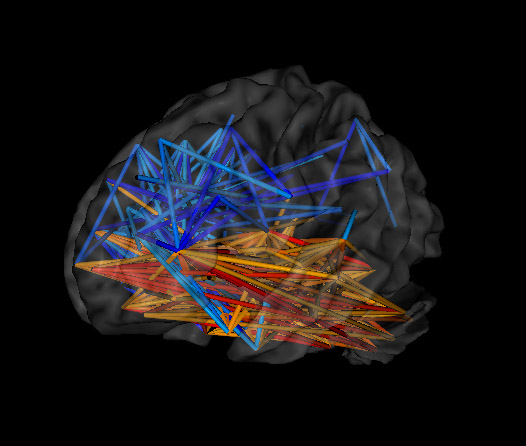

EEG brain scans showing typical results from autism loreta neurofeedback showing signs of autism Autism / spectrum results from loreta neurofeedback

Atypical connectivity patterns within the brain seem to explain some of the challenges experienced by those with ASD. EEG and fMRI imaging demonstrate a surplus of synapses and connections between certain regions, which can make it difficult for a person to switch between tasks and ideas. This might underlie the repetitive and restrictive behaviors often exhibited by those with ASD. Hyperconnectivity and inefficient communication between neurons can also affect other important processes such as motor control, interpretation of social cues, and language production/analysis.

Areas of the brain associated with sensory integration and processing also tend to show more “randomized” activity in the EEGs of those with ASD. Such activity can make it more difficult for individuals to process and tolerate sensory information. Additionally, some ASD individuals show an excess of slow brainwave frequencies (e.g., delta/theta) throughout the brain, leading to significant impairments in learning and cognitive processing. They may also show an excess of faster frequencies in regions related to stress and anxiety, leading to heightened emotional reactivity.

Furthermore, the brains of those diagnosed with ASD often show reduced activation levels within imitation-related brain areas when compared to individuals without ASD. Limited functioning of these areas is thought to contribute to a variety of ASD symptoms, especially those related to social interactions.